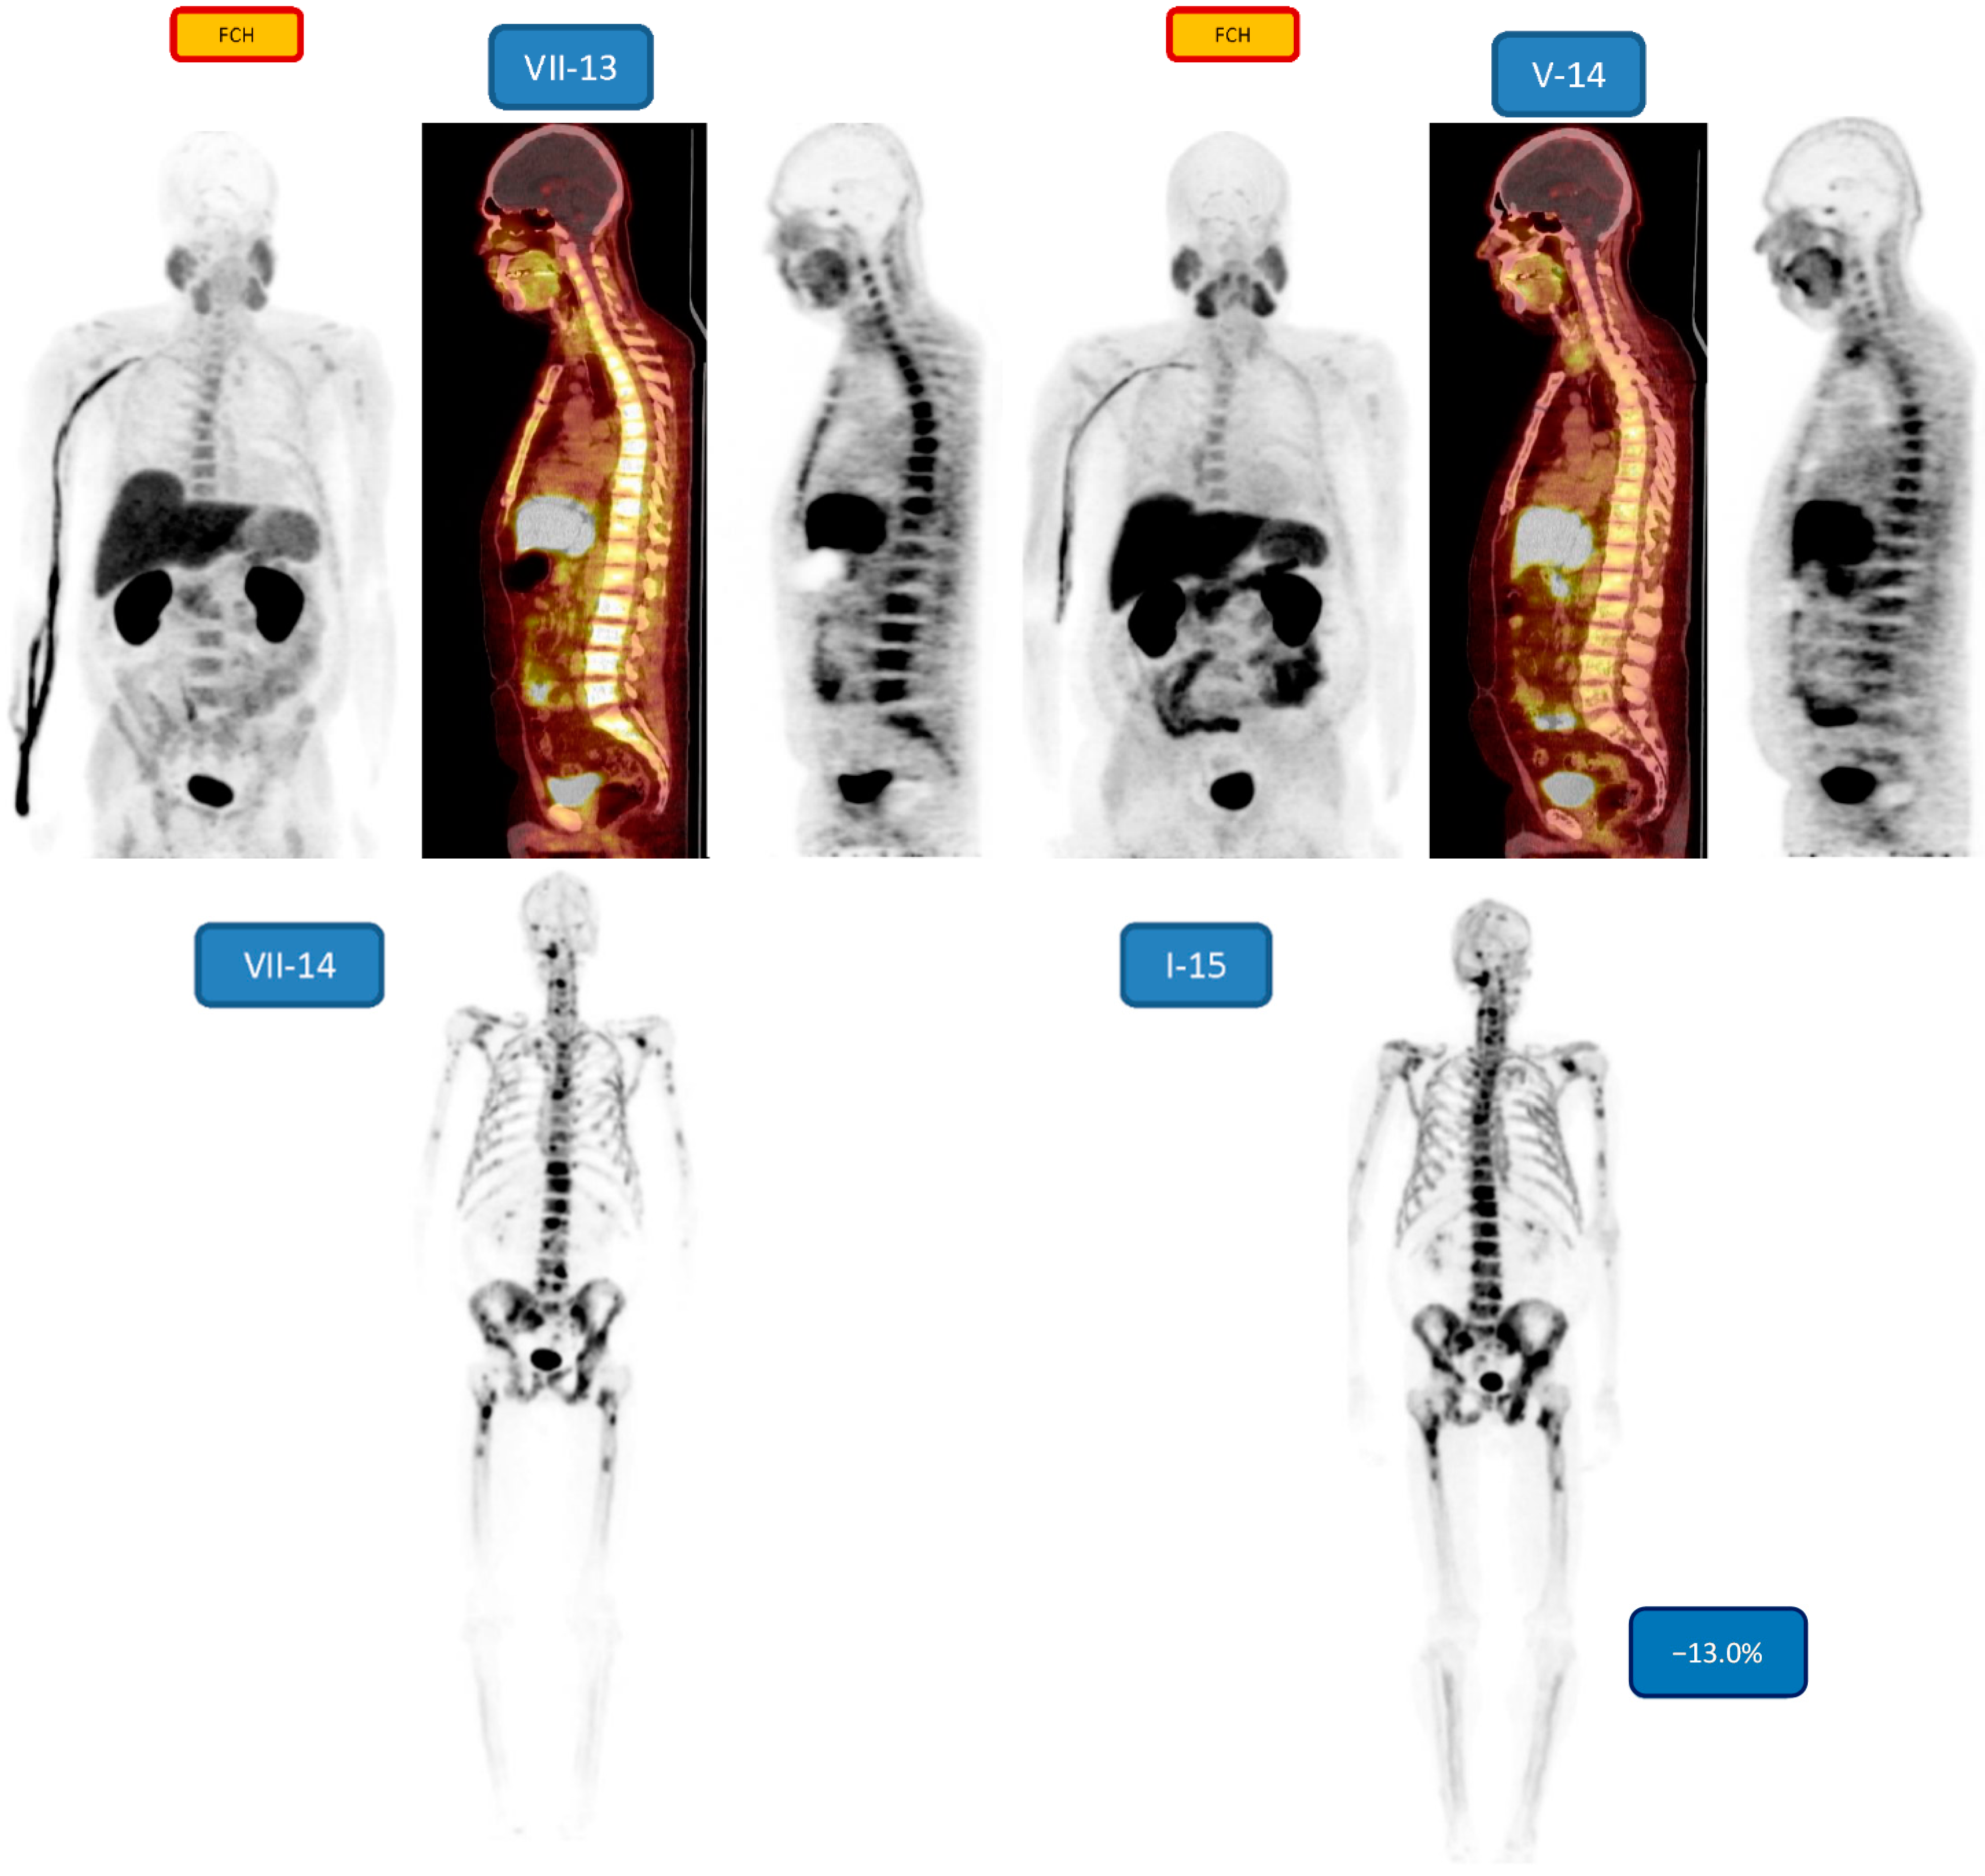

| 4 m/49 | Bone 3/3 | nd/−13.0 | 6 31.57 MBq | PD/SD | Lupron,Denosumab, Abiraterone |

| 7 m/56 | Bone 3/3 | nd/−11.4 | 6 22.78 MBq | PR | Lupron, Denosumab, Abiraterone |